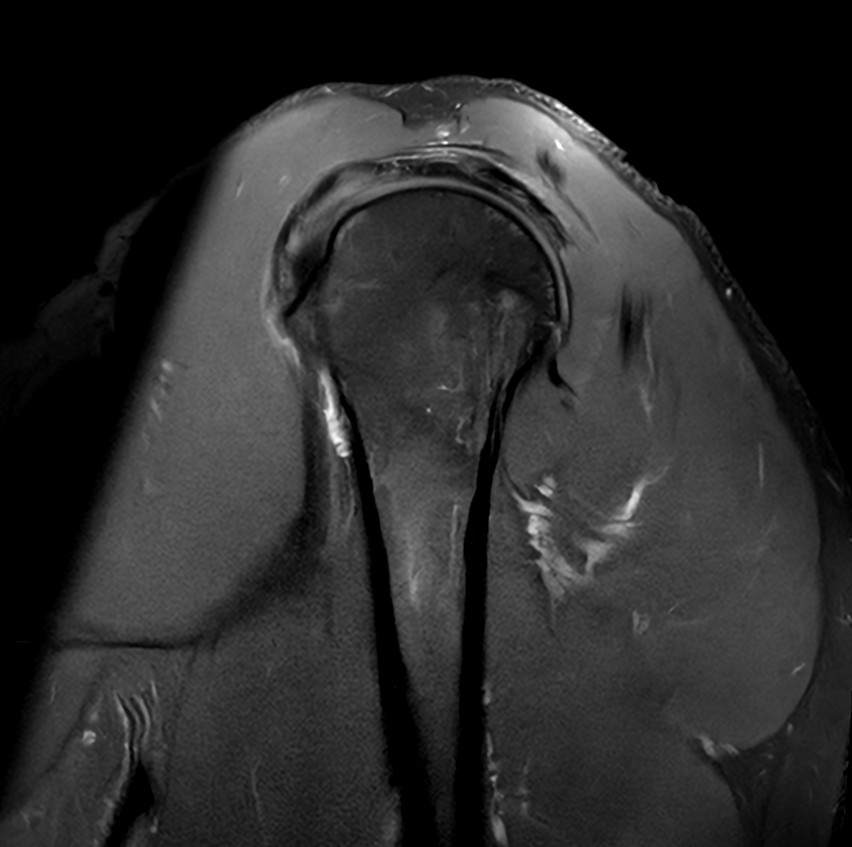

High quality Shoulder imaging with SmartSpeed Precise